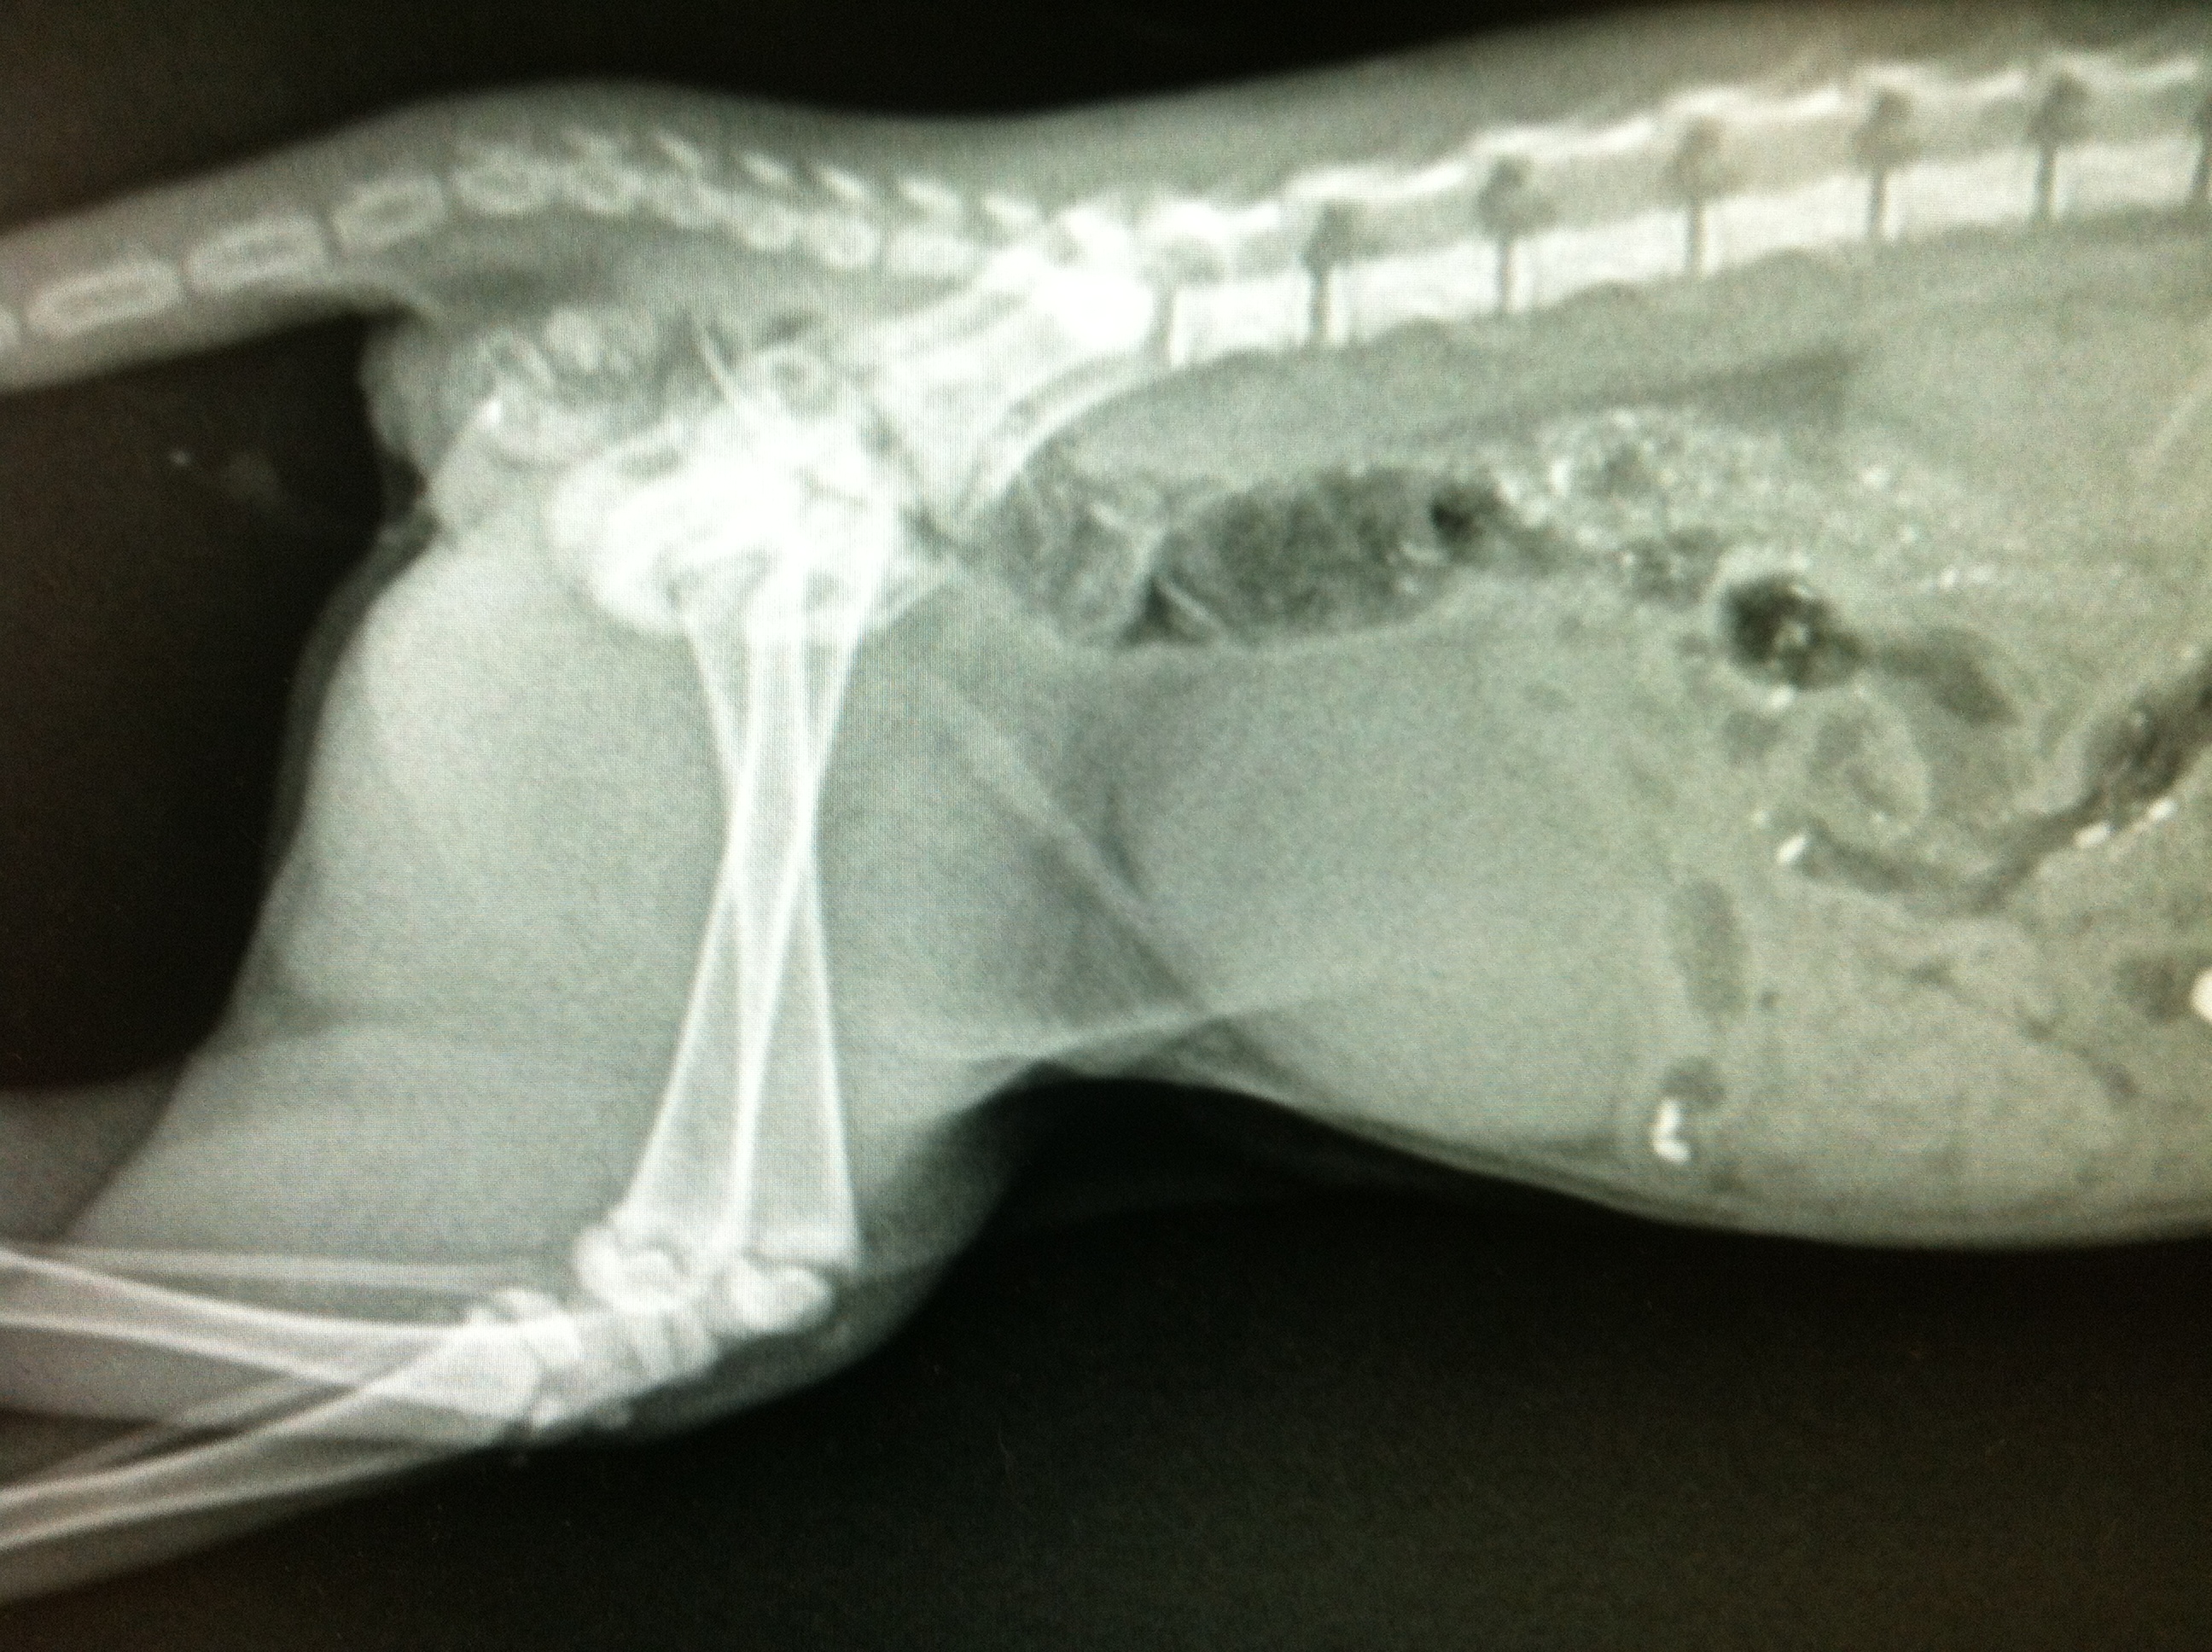

Wesson was transferred to the caring volunteers at Mended Hearts Rescue and taken to a local veterinarian for evaluation of an injury to his right front leg. The x-rays of his leg showed a severe fracture of the humerus (upper arm bone) and a bullet lodged within the surrounding muscle.

I love my friends, and I also love my new iphone. (See, I told you it’d seem random, just hang in there) Within moments I was able to text a picture of the x-rays to three of my orthopedic surgeon friends and, within moments, I got three definitive opinions in favor of limb amputation. (Props to Dr. Amy Fauber, Dr. Todd Reicks, and Dr. Aaron Wehrenberg for their fast, free orthopedic consults!)

The location of the trauma meant permanent nerve damage for poor Wesson. This would mean chronic pain and lameness if left alone. Once the verdict was in, Wesson was immediately scheduled for surgery.